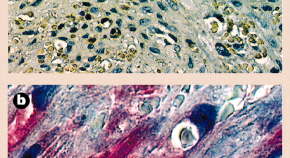

• Kaposi's sarcoma (KS) is the most common cancer in HIV-infected untreated individuals. Kaposi's sarcoma-associated herpesvirus (KSHV) is the infectious cause of KS. This Review discusses the insights into the remarkable mechanisms through which KSHV can induce KS that have been gained in the past 15 years.

Volume: 10, P: 707-719

• Kaposi sarcoma-associated herpesvirus (KSHV) is involved in the etiopathogenesis of Kaposi sarcoma and certain lymphoproliferative disorders. Open reading frame (ORF) 73 encodes the main immunogenic latent nuclear antigen (LNA-1) of KSHV. LNA-1 maintains the KSHV episome and tethers the viral genome to chromatin during mitosis. In addition, LNA-1 interacts with p53 and represses its transcriptional activity. Here we show that LNA-1 also interacts with the retinoblastoma protein. LNA-1 transactivated an artificial promoter carrying the cell cycle transcription factor E2F DNA-binding sequences and also upregulated the cyclin E (CCNE1) promoter, but not the B-myb (MYBL2) promoter. LNA-1 overcame the flat-cell phenotype induced by retinoblastoma protein in Saos2 cells. In cooperation with the cellular oncogene Harvey rat sarcoma viral oncogene homolog (Hras), LNA-1 transformed primary rat embryo fibroblasts and rendered them tumorigenic. These findings indicate that LNA-1 acts as a transcription co-factor and may contribute to KSHV-induced oncogenesis by targeting the retinoblastoma protein–E2F transcriptional regulatory pathway

Volume: 6, P: 1121-1127